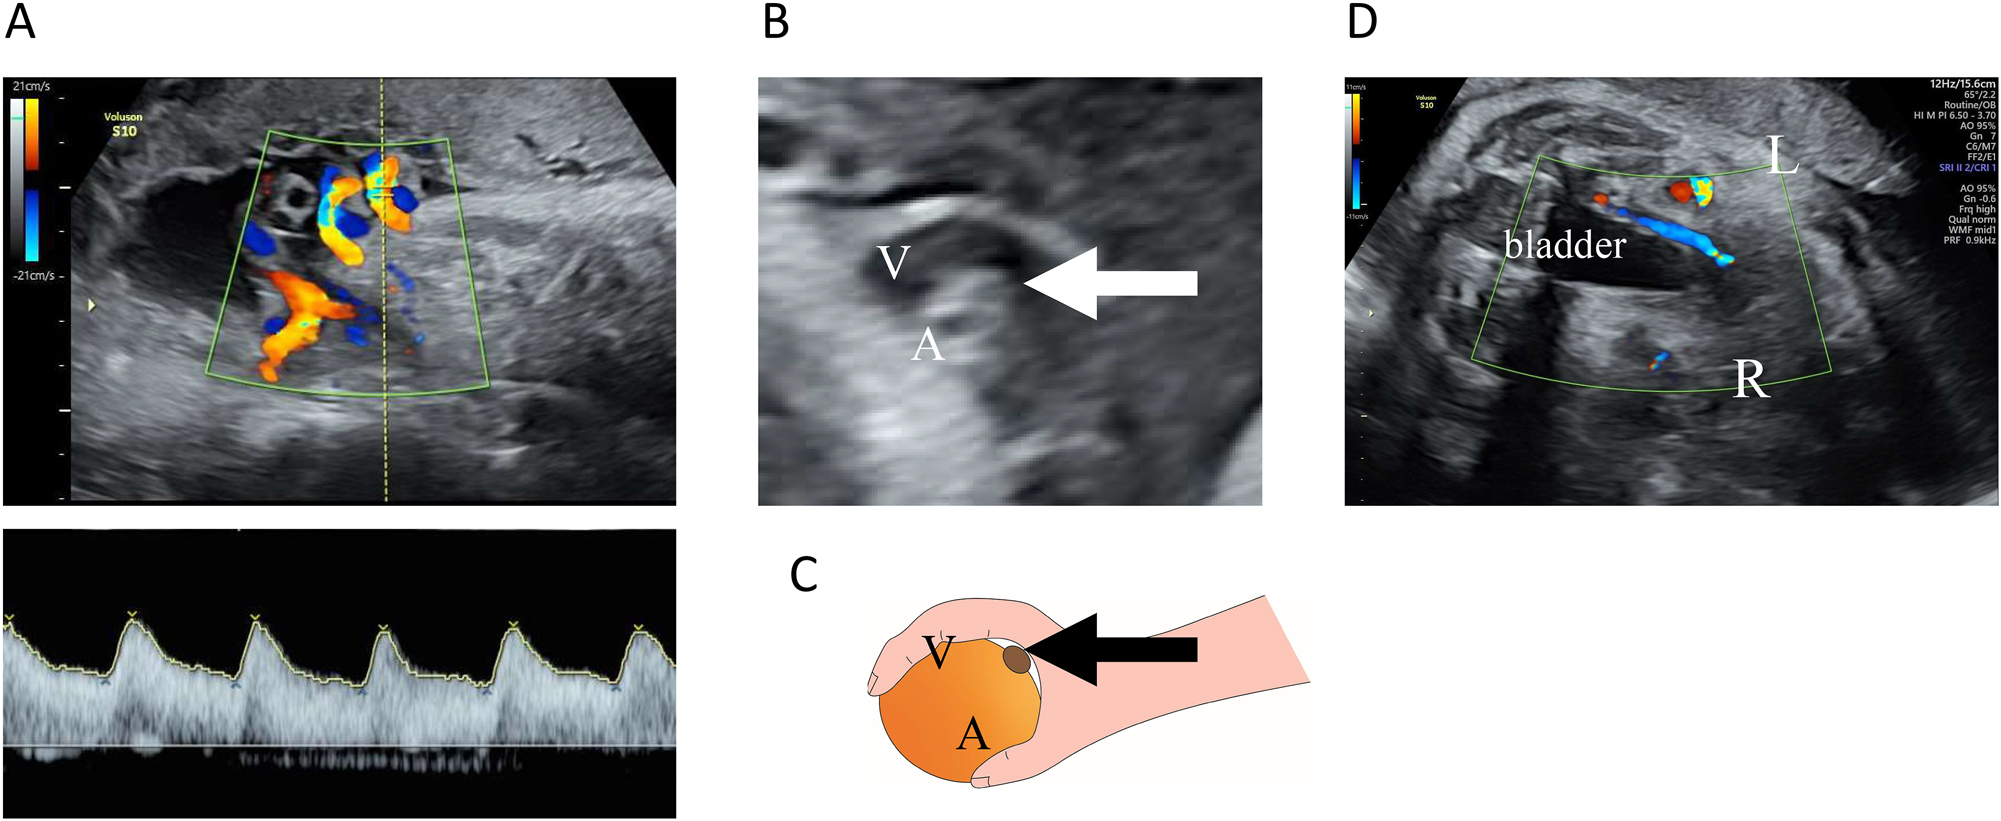

However, at 34 weeks and 5 days of gestation, the patient presented to the hospital after noticing reduced fetal movements. We confirmed decreased fetal movements via transabdominal ultrasound. The patient’s biophysical profile score was 4 out of 10, with positive findings for fetal tone and amniotic fluid pocket; however, there were no observed fetal breathing movements, fetal gross body movements, or reactive non-stress test. A fetal ultrasound revealed a fetal weight of 2,202 g (38th percentile). Figure 1 illustrates the estimated fetal weights at antenatal check-ups up to that point. Estimated fetal weight and percentiles were calculated based on the Japan Society of Ultrasonics in Medicine (JSUM) 2001 guidelines. Color flow mapping ultrasound showed blood flow arrest over a wide area in one umbilical artery; however, pulsed wave Doppler revealed no abnormal findings in the waveform of the umbilical artery with blood flow (Figure 2A). In addition, a strongly curved umbilical vein surrounding a blood-filled umbilical artery was seen, with small echoicity between these vessels. This finding was consistent with the ‘orange grab sign’ previously reported in UAT cases [1] (Figure 2B and C). Additionally, cessation of blood flow was observed in the right umbilical artery running along the right side of the fetal bladder (Figure 2D). Other blood flow assessments (e.g., in the left umbilical artery, middle cerebral artery, and venous duct assessments) did not reveal anomalies in waveform, flow velocity, or resistance. All ultrasound images were acquired using a Voluson S10 ultrasound machine and the RM6C transducer (GE Healthcare Japan, Tokyo, Japan). Based on these observations, we established a diagnosis of non-reassuring fetal status, and with the patient’s consent, performed an emergency cesarean section. The neonate’s Apgar scores were 8 and 9 after 1 and 5 min, respectively. Umbilical artery blood gas analysis performed immediately after birth showed a pH of 7.248 and a base excess of −3.8. The mother and neonate had good postoperative courses and were discharged as normal. We detected no abnormalities in the child at the 1-month check-up.

Ultrasound examination. (A) Transabdominal ultrasound images of the umbilical arteries and veins. Color flow mapping images of the umbilical cord blood flow. An opposing blood flow was seen in only one artery, indicating extensive disruption of blood flow in one umbilical artery. No abnormal findings were observed in the pulsed Doppler waveform for the umbilical artery with blood flow. (B and C) The ‘orange grab sign’ in B mode. A highly curved umbilical vein (V) surrounding an umbilical artery with blood flow (A) and an umbilical artery with an interrupted blood flow (arrow) was seen between them. (D) Horizontal section at the level of the fetal bladder. The right umbilical artery running on the right side of the bladder was observed to have an interrupted blood flow.

Fetal ultrasound of a normal umbilical cord reveals one large vessel (umbilical vein) and two small vessels (umbilical arteries) in the cross-section. Color Doppler distinguishes these vessels using different colors and confirms their opposite blood flow directions. In UAT, blood flow ceases in one of the umbilical arteries, leaving only one vessel of each type (Figure 2A), and only one of the umbilical arteries is observed running alongside the fetal bladder (shown in Figure 2D). Besides, these findings are observed in single umbilical artery (SUA) cases, which can create diagnostic challenges [4]. SUA can result from congenital aplasia or early pregnancy atresia [5], both of which can be diagnosed by around 12 weeks of gestation [6]. In contrast, UAT typically occurs in the later stages of pregnancy. Essentially, SUA cases present with two visible vessels and blood flows from the outset, whereas UAT manifests as a reduction from three visible blood flows and vessels to two blood flows and three vessels. The presence of three vessels even after the onset of UAT is crucial in differentiating UAT from SUA. By comparing previous ultrasound findings of the umbilical cord, UAT can be differentiated from SUA.

The “orange grab sign” (Figure 2B and C), previously identified in umbilical cords with UAT [1], is considered characteristic of UAT and can be identified without comparing new and previous umbilical findings [7, 8]. Moreover, this sign reflects the presence of three vessels and is not observed when there are only two vessels.